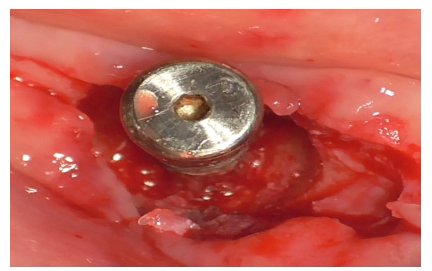

Implant decontamination commenced with an ultrasonic tip (Figure 17) and continued with the diamond ball insert (ES015T) of the Ultrasonic Device (Figure 18).

Figure 17

Figure 18